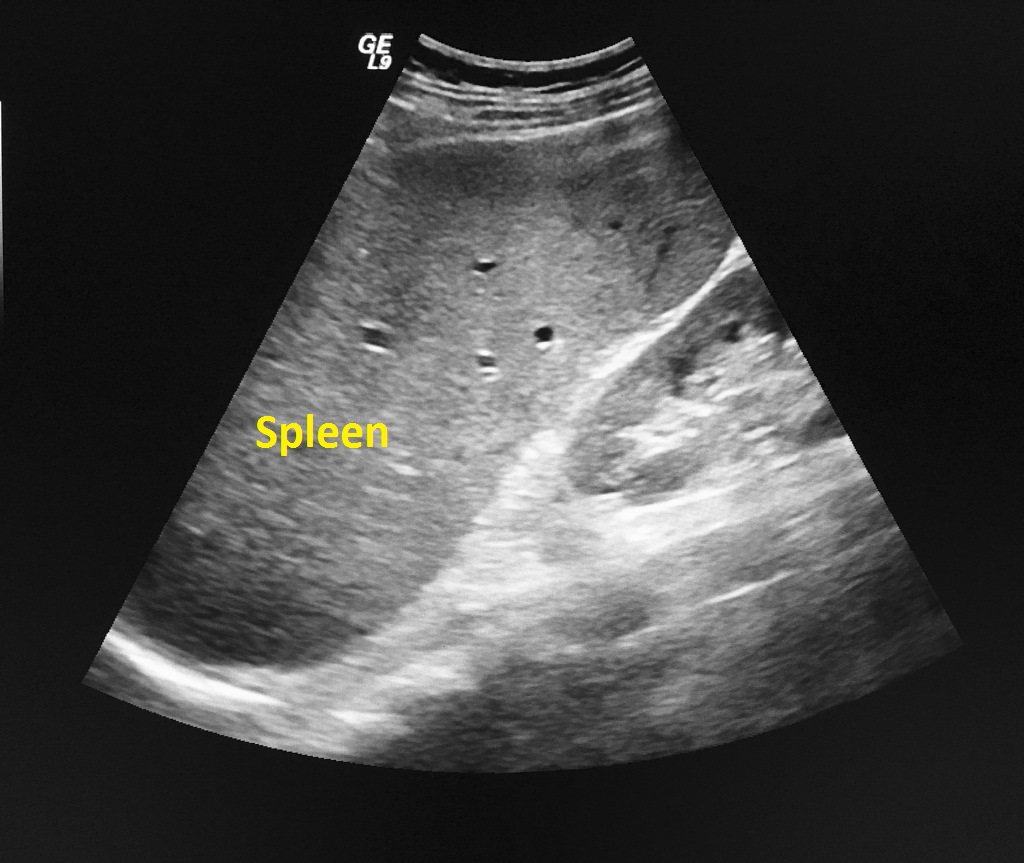

LIVER ULTRASOUND 👨🏽💻Ultrasound of the liver is a key tool in …

Liver Ultrasound – Dr Iain Duncan

Non-invasive evaluation of liver cirrhosis using ultrasound – Clinical …

Normal ultrasound liver pattern. Echogenicity and echodensity of the …

Liver Anatomy and Protocol basics – Sonographic Tendencies | Liver …

MBBS Medicine (Humanity First): Liver Ultrasound | Ultrasound …

Liver Anatomy and Protocol basics – Sonographic Tendencies | Medical …

Ultrasound of the liver, biliary tract, and pancreas | Abdominal Key

Practice of Ultrasound: Part 13 — Liver fat and fibrosis

Non-invasive evaluation of liver cirrhosis using ultrasound – Clinical …

Practice of Ultrasound: Part 13 — Liver fat and fibrosis

Imaging Studies of the Liver: Ultrasound

Ultrasound Image of Liver Cirrhosis Stock Photo – Image of healthcare …

Cirrhosis echocardiography or ultrasound – wikidoc